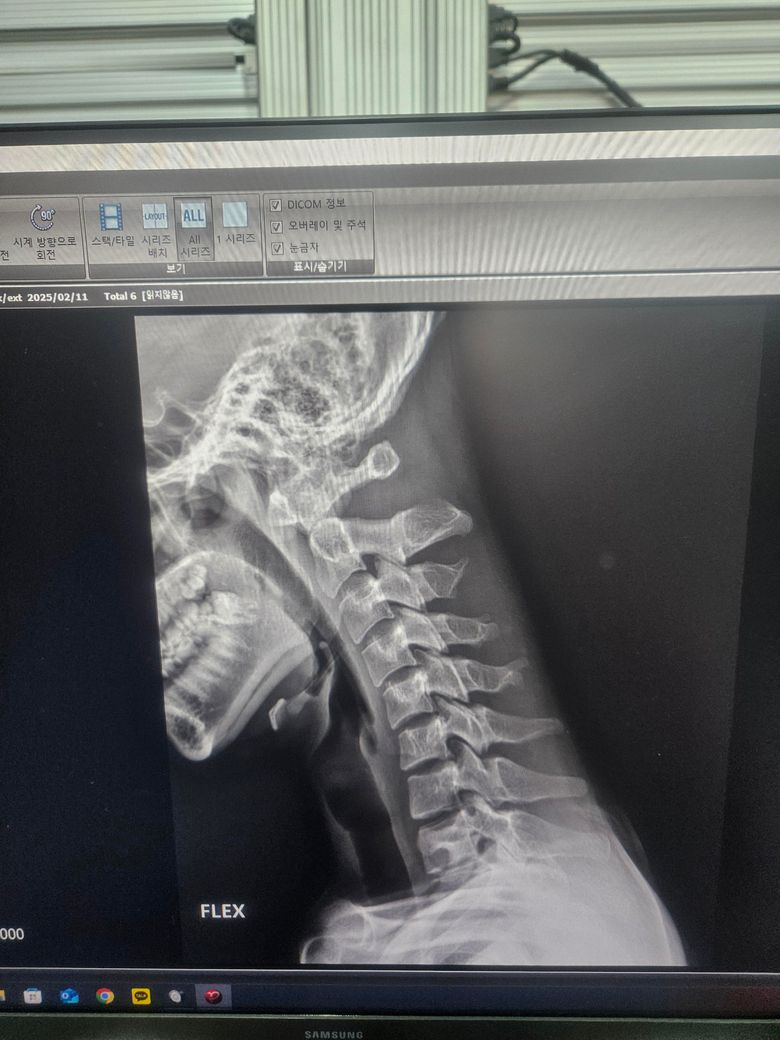

경추 불안정증인가요? 아시는분 제발 ㅜㅜ

몇번째 글 올리는건지 모르겠네요 경추 1번 과 2번 사이가 3mm미만이면 정상범위라는데 저는 몇미리인가요 불안정증이 있는건가요 ㅜㅜ

단순히 영상 사진을 다시 사진으로 찍은 자료만으론 판단 불가합니다. 세팅을 어떻게 했느냐에 따라 보이는 길이와 실제 길이가 차이가 나기 때문이죠. 사진을 다시 사진으로 찍으면서 생기는 오류도 있을수 있구요.

영상 찍은 병원 담당 의사에게 물어보는게 제일 정확합니다